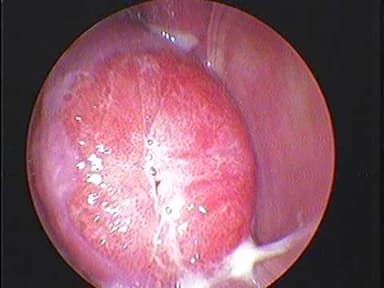

Viêm lộ tuyến cổ tử cung

Đây là tình trạng cổ tử cung bị viêm nhiễm do vi khuẩn, nấm hoặc ký sinh trùng gây ra.

Khi bị viêm lộ tuyến cổ tử cung, chị em sẽ thấy xuất hiện các triệu chứng như: khí hư xuất hiện nhiều, đau vùng xương chậu hoặc đau sau khi quan hệ tình dục, tiểu buốt, tiểu dắt, bí tiểu, khó mang thai…

Chị em cũng có thể gặp phải bệnh viêm lộ tuyến cổ tử cung

Bệnh viêm lộ tuyến cổ tử cung nếu không được điều trị triệt để và kịp thời có thể gây viêm tắc vòi trứng, viêm nội mạc tử cung, viêm tiểu khung, vô sinh.